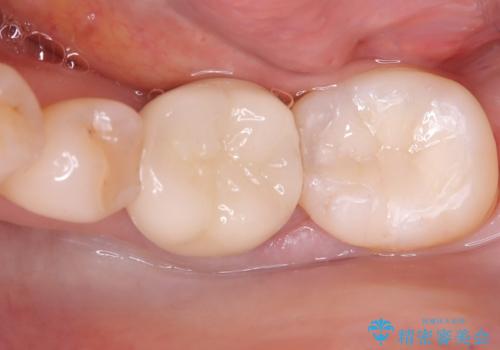

セラミッククラウンによる奥歯の修復

担当医 河口智英